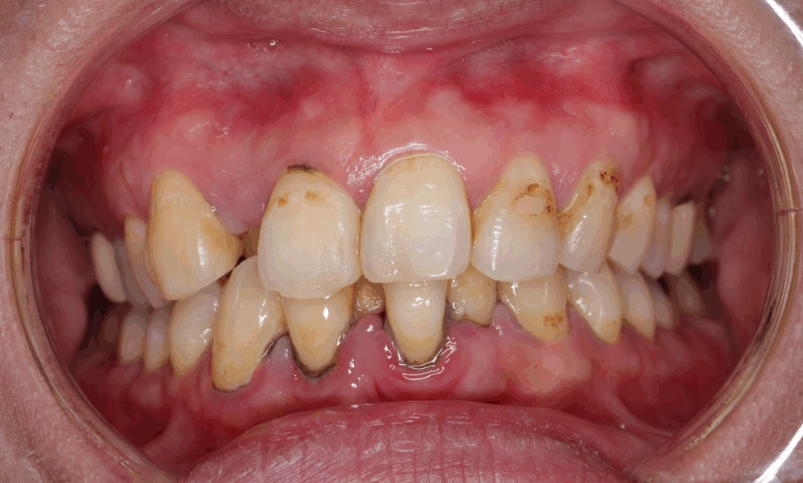

它剛形成時是軟的,可以用物理方式(刷牙)清除。但如果你沒清乾淨,大約24到72小時後,它就會開始礦化,吸收唾液中的鈣質,逐漸變硬成為「牙結石」。一旦變成牙結石,就像水泥糊在牆上,靠刷牙是絕對刷不掉的,必須由牙醫透過專業器械(如超音波洗牙機)才能清除。根據美國牙科協會的資料,牙菌斑是導致齲齒和牙周病的元兇。

很多人一把牙刷用半年,刷毛都開花了還捨不得換。開花的刷毛清潔效率極低,根本無法有效刮除牙菌斑。另一種極端是選用刷毛過硬的牙刷,以為這樣才能刷得乾淨,結果反而傷害牙齦,導致萎縮,讓牙根暴露處更容易堆積牙菌斑。

3. 忽略了最重要的區域:牙縫